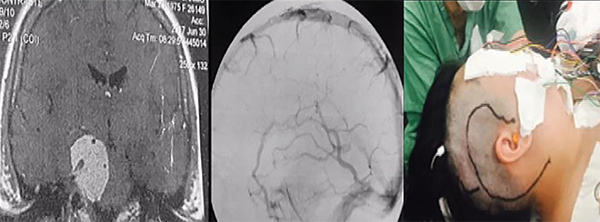

La resonancia magnética muestra la extensión y la relación de la lesión con el tronco encefálico, vasos y pares craneales, demostrando claramente cuando se produce el desplazamiento y la compresión de las estructuras normales. La resonancia magnética con gandolinio a menudo demuestra una lesión con realce intenso y homogéneo. En T1 el tumor tiene un aspecto isointenso, mientras que en TR largo (T2 y Flair) es hiperintenso. Además, es bastante hidratado y tiene una superficie externa ligeramente lobulada. La confirmación de edema en T2 en el tronco encefálico caracteriza la invasión de la aracnoides y generalmente es un signo de mal pronóstico cuando se trata de resecar el tumor por completo.3,4 La resonancia magnética de alta definición es esencial para la planificación quirúrgica. La vascularización del tumor y su relación con los vasos importantes se pueden demostrar mediante angiorresonancia magnética, angio-tomografía computarizada tridimensional multicorte o mediante arteriografía digital. Es importante estudiar el suministro vascular y los desplazamientos, estenosis u oclusiones de las arterias basilar, carótida interna y sus ramas. Incluso en los casos en que la arteria basilar está involucrada por el tumor hay un buen plano de clivaje con éste. Estos tumores generalmente son irrigados por ramas de la arteria carótida externa y por ramas del tronco meningohipofisiario (arteria de Bernasconi- Cassinari) generalmente aumentado.20,21 Los tumores hipervascularizados se pueden embolizar en el período preoperatorio reciente, pero generalmente la coagulación de la base del tumor al comienzo de la cirugía es suficiente para prevenir un sangrado mayor. La ubicación del drenaje de la vena de Labbé es crucial cuando se pretenden llevar a cabo abordajes en los que sea necesaria la retracción del lóbulo temporal, como un abordaje petroso (Figura 3). Su visualización preoperatoria se puede obtener mediante angio-tomografía computarizada - venografía o angiografía de fase venosa. Este conocimiento preoperatorio es muy importante para planificar el abordaje quirúrgico a fin de preservar la vena de Labbé y prevenir complicaciones venosas.22

Los abordajes petrosos son pre-sigmoideo retrolaberíntico, pre-sigmoideo translaberíntico y petrosectomía total. Estos abordajes se utilizan cuando la lesión se encuentra en la fosa media, fosa posterior y la región clivus (Figuras 3 y 4). Si el paciente tiene buena audición previa, se prefiere el acceso pre-sigmoideo retrolaberíntico. Cuando no hay audición preservada es posible extirpar los canales semicirculares, y este abordaje se denomina pre-sigmoideo translaberíntico. Para los tumores gigantes que cruzan la línea media en la región prepontina es necesario un abordaje más lateral y extenso, a través de la petrosectomía total (petrosectomía posterior asociada con la petrosectomía anterior). La cirugía se realiza con el paciente en posición decúbito dorsal, con la cabeza vuelta hacia el lado opuesto. La incisión en la piel se realiza en forma semicircular a partir la región temporal, cuatro centímetros por encima del arco cigomático, pasando tres centímetros detrás de la oreja, extendiéndose dos centímetros detrás de la punta del mastoides. Para evitar fístula del LCR postoperatoria, se utiliza la reconstrucción de la base del cráneo con la fascia temporal, que se diseca con el periostio mastoideo, la fascia craneocervical y el músculo esternocleidomastoideo, que se separa de su inserción, formando un gran colgajo vascularizado que es girado para atrás al final de la cirugía para cubrir todo el campo quirúrgico. La corteza mastoidea es drenada, identificándose el laberinto y el canal del nervio facial. Estos canales no son abiertos. Se realizan dos trepanaciones por encima y dos por debajo del seno sigmoideo y, con una broca de alta rotación, se realiza una craneotomía, exponiendo las fosas media y posterior (retrosigmoide). Los senos petroso superior, sigmoideo y transverso son expuestos. Las celdas mastoideas retrofaciales se eliminan hasta el bulbo yugular. La duramadre anterior es expuesta al seno sigmoideo. Se extraen las células cigomáticas y supralaberínticas, manteniendo intactos los canales semicirculares y el oído medio. El seno petroso superior se secciona anterior a su entrada en el seno sigmoideo. Antes de esta maniobra, debe conectarse con un punto o con microclips. Luego, se realiza una incisión en el tentorio, inicialmente perpendicular al seno petroso superior de dos a tres centímetros y luego medialmente, paralelo al seno transverso en otros tres centímetros. Esta maniobra permite una amplia exposición del cerebelo, separándolo a partir del aspecto posterior del lóbulo temporal en "libro abierto". Se debe tener cuidado para preservar la vena de Labbé, que tiene una anatomía variable y generalmente ingresa al seno transverso diez milímetros antes de su unión con el seno sigmoideo. La evaluación preoperatoria de la anatomía venosa es esencial para planificar este abordaje. La incisión del tentorio se continúa hasta la incisión donde se expone y preserva el IV par craneal. Algunas pequeñas venas puente basales en la base anterior del lóbulo temporal se coagulan y cortan, permitiendo una amplia exposición subtemporal. Se debe evitar la colocación de espátulas fijas con Leyla apoyando el lóbulo temporal y el cerebelo. En general, la espatulación leve realizada por el auxiliar de manera no continua es suficiente para exponer toda la región petroclival de los pares craneales III a VII y VIII. El nervio trigémino generalmente se puede ver desplazado posterior y superiormente. El tumor se desvasculariza por la coagulación bipolar de su inserción dural. Posteriormente, la resección intracapsular fragmentada del tumor se realiza con un aspirador ultrasónico, realizando una citorreducción del tumor, que permite la disección de la cápsula tumoral de los nervios, la arteria basilar y las arterias cerebelosa superior y cerebral posterior. El nervio abducente es muy delgado y frágil. El canal de Dorello se encuentra medial a los pares craneales VII y VIII, y esta región debe abordarse solo después de una resección extensa del tumor. Las extensiones tumorales de la parte posterior del seno cavernoso se resecan después del nervio trigémino. Toda infiltración del hueso petroso y el clivus se elimina con una broca de diamante. Después de la extracción total, la duramadre se cierra herméticamente o con un injerto de fascia y pegamento de fibrina. El abordaje presigmoideo translaberíntico es similar, pero con la eliminación adicional del laberinto al drenar los canales semicirculares, lo que agregará una exposición de aproximadamente 1,5 centímetros de cirugía y permitirá una mejor vista de las estructuras de la línea media. Esta apertura de los canales semicirculares causa sordera y sólo está indicada para pacientes sin audición viable previa.1

Figura 3:Resonancia magnética con gadolinio, corte coronal, que muestra un componente tumoral en la fosa posterior y en la fosa media. Caso ideal para el abordaje petroso (izquierda). Angiografía de fase venosa que muestra drenaje de la vena de Labbé en la unión del sigmoide con el transverso, sin contraindicar el abordaje petroso (centro). Incisión del abordaje petroso (también conocido como abordaje presigmoideo (supra/infratentorial) utilizado en este caso (derecha).